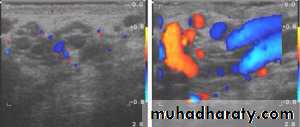

Doppler ultrasound scan will confirm the absence of the blood supply to the affected testis

Investigations: Scrotal Doppler U/S